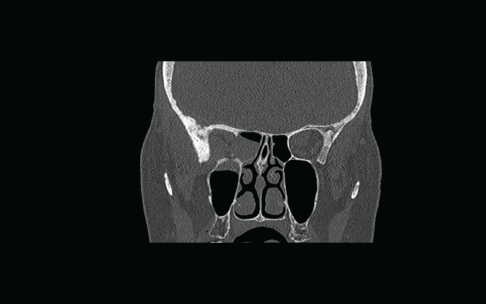

Flexible nasendoscopy was performed in ENT outpatient clinic and did not identify any lesions or mucosal abnormality. Her most recent bone scan revealed an increased uptake in the right ethmoid sinus as well as the other areas noted previously. The outcome is similar to her original scan in 2009 as well as her subsequent scans. Due to her new symptoms, she was investigated further with a computerized tomography (CT) scan of her sinuses. This showed minor right-sided ethmoid sinus involvement and soft tissue density in the right sphenoid and maxillary sinuses (Figure 2).

Figure 2: Coronal CT scan showing non-specific findings of “mucosal disease” involving the right maxillary, ethmoid, and sphenoid sinuses. An erosion of the lateral wall of right sphenoid is also noted.